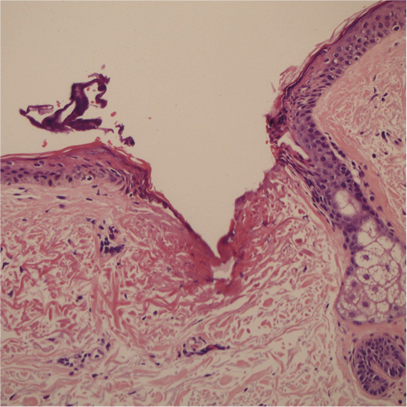

放大皮膚切片圖100倍後能清晰看到療程後表皮即時形成微創傷口。

療程後即時

病人MZ: 能量80%---皮膚顯示燒焦灶,直徑為0.26毫米,穿透深度: 0.55毫米

病人MZ

皮膚顯示燒焦灶,

直徑為0.26毫米 穿透深度: 0.55毫米